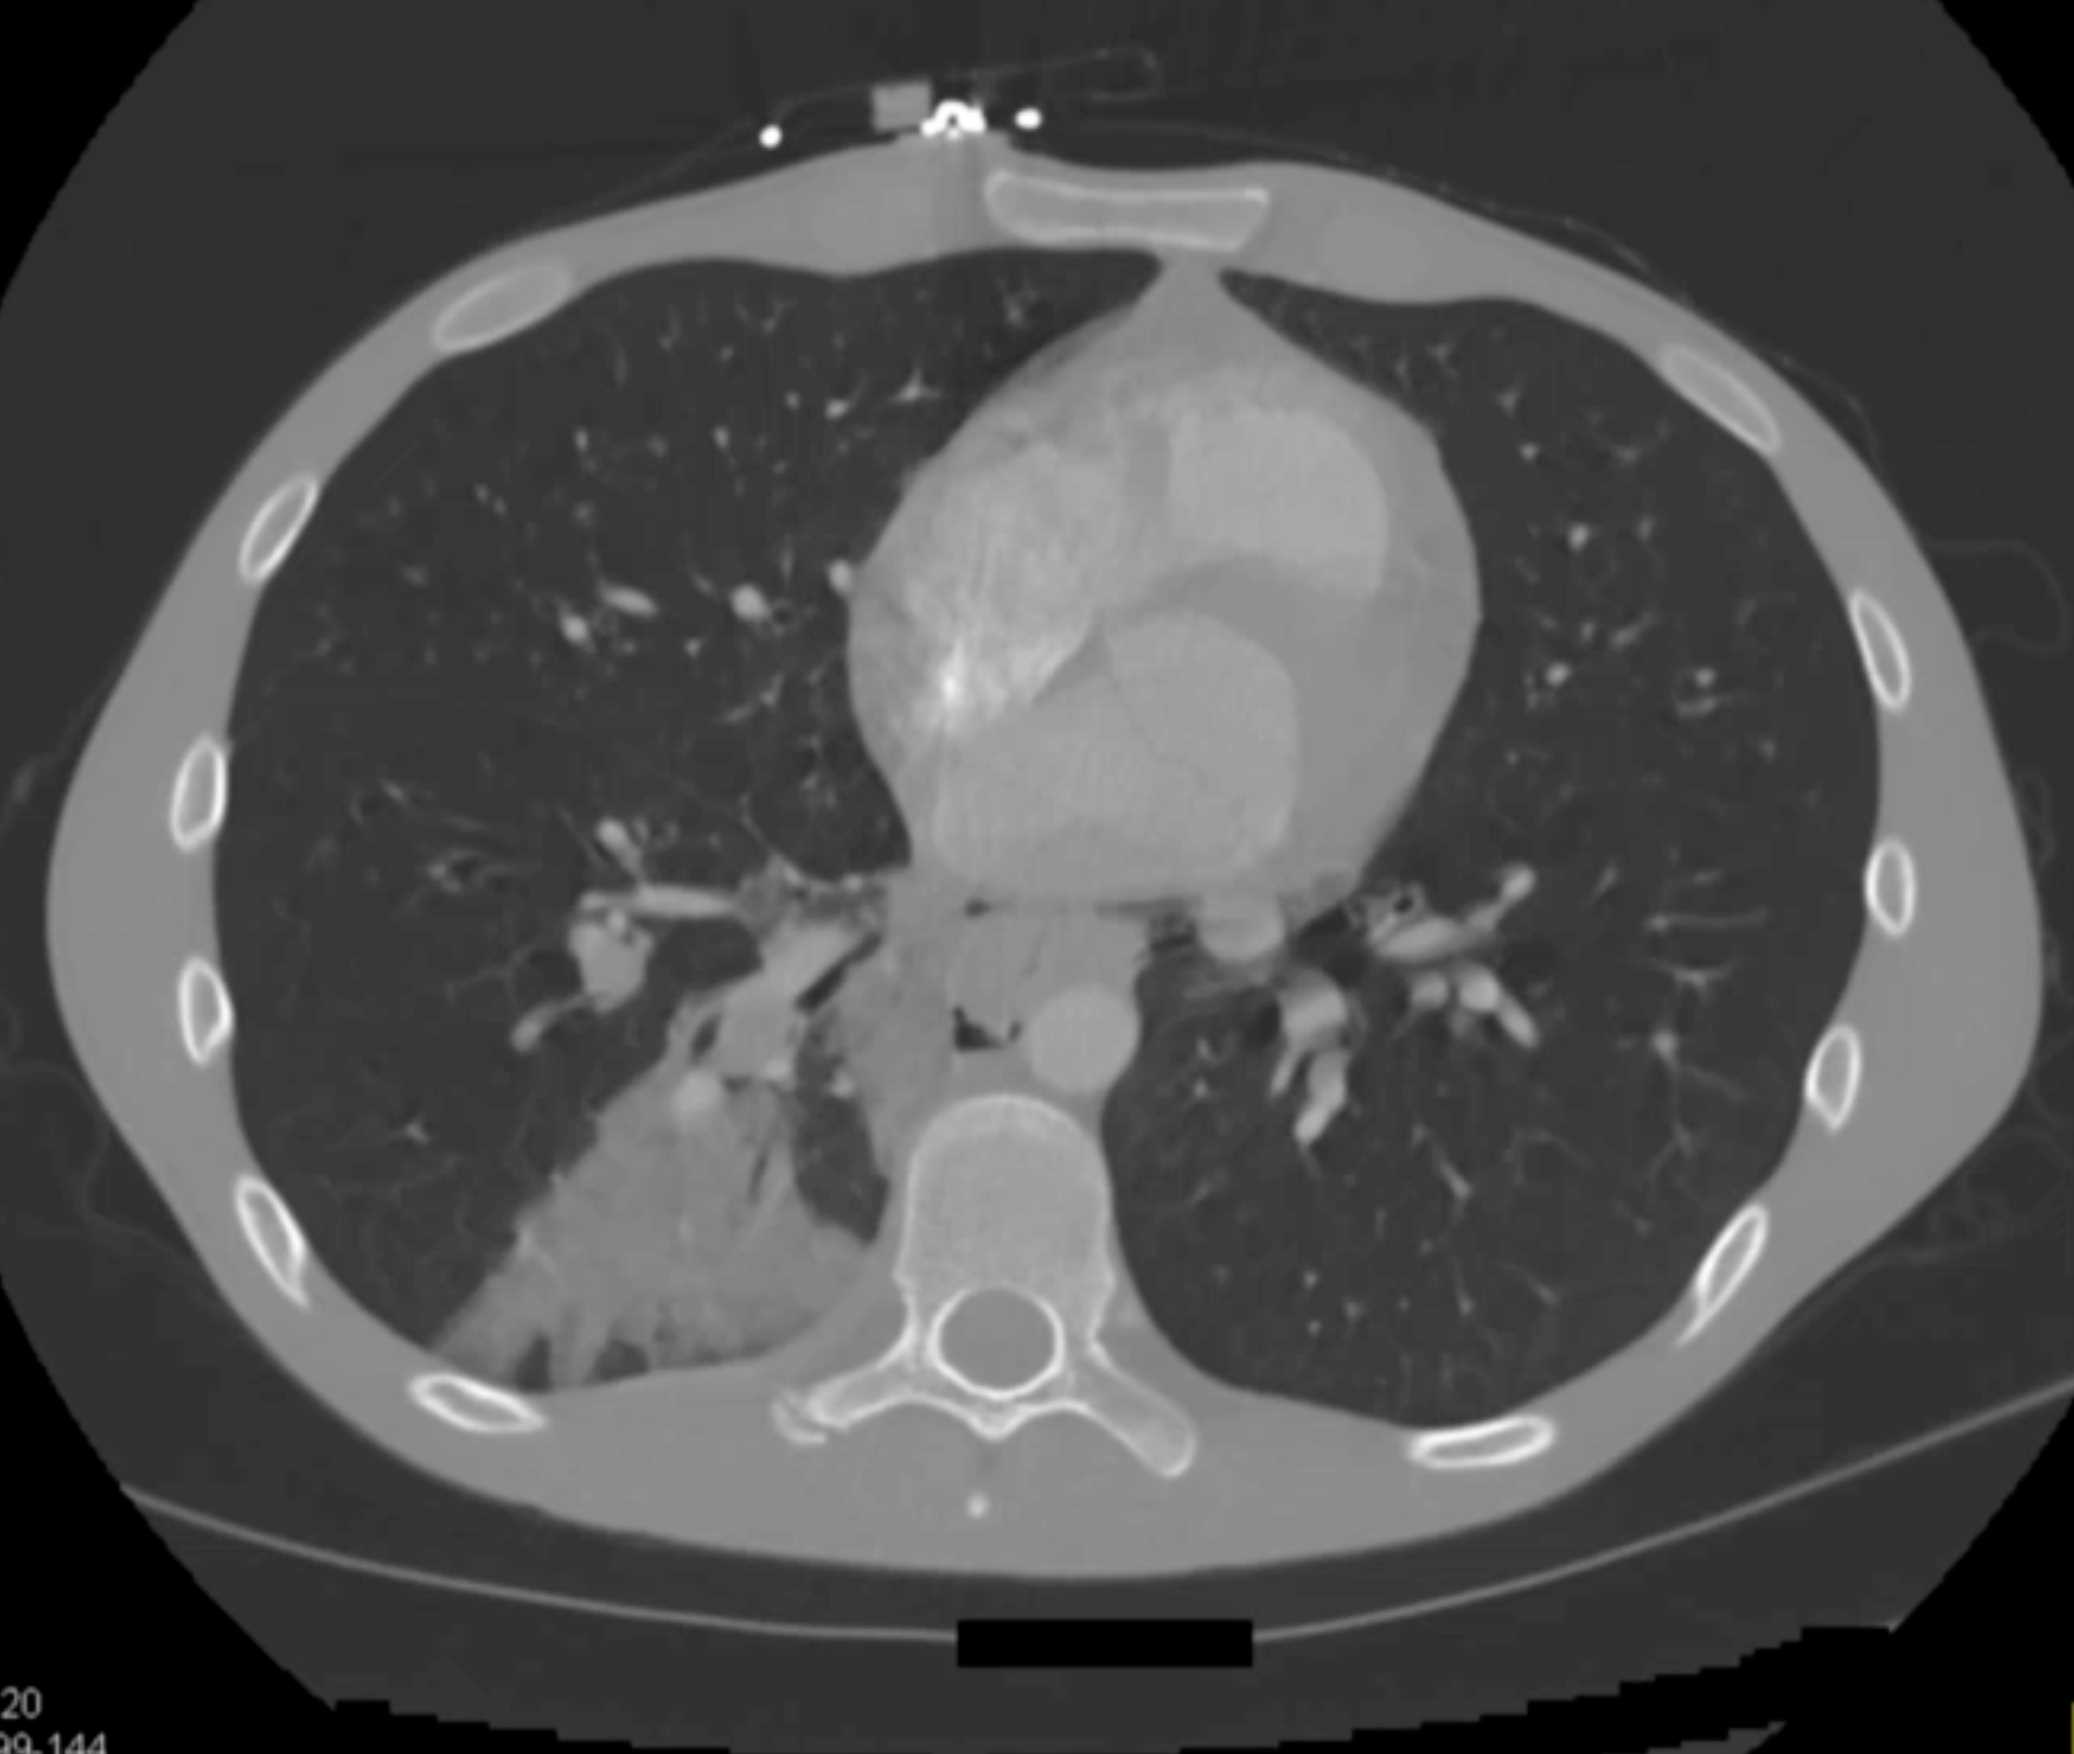

Large Cell Lymphoma